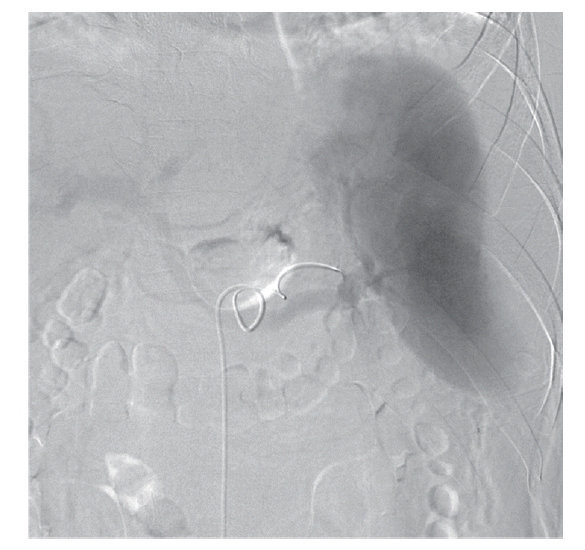

The patient’s hemoglobin level was 14.4 g/dl 1 day before visiting the Emergency Department and decreased to 11.0 g/dl. The concentration then rapidly dropped to 9.5 g/dl, and the patient received a blood transfusion. The patient also had thrombocytopenia (71 k/μl) with 33 IU/L AST, 44 IU/L ALT, 25.4 mg/dl BUN, and 1.66 mg/dl creatinine. He was admitted to the intensive care unit for a conservative treatment. Despite transfusion, the hemoglobin levels and blood pressure remained unstable. On the second day of hospitalization, a splenic angiogram was performed. No definitive extravasation of contrast media was observed, but contour irregularity was noted in the lateral lower margin (Fig. 3). Embolization was performed with 7 coils (10×4 mm, 8×4 mm, 6×2 mm; Cook, Bloomington, Minneapolis, USA) at the distal splenic artery level (Fig. 4).

Fig. 3.

No definitive extravasation of contrast media was viewed on the splenic angiogram, but contour irregularity was noted in the lateral lower margin.

kjp-53-2-215f3.gif